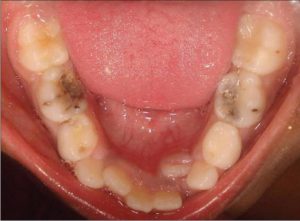

идет подготовка к смене зубов), сохранять временный зуб нецелесообразно. В связи с этим нередко прибегают к экстракции (удалению). Так называемый «бутылочный кариес» чаще всего поражает резцы и клыки в пришеечной области. Заболевание характерно для детей до 3 лет. В литературе можно встретить и другое название – «молочный кариес».

Причина развития данной патологии – неправильный режим питания в сочетании с недостаточно высоким уровнем гигиены полости рта. К этой разновидности кариеса часто приводит сосание сладких (в т. ч. молочных) напитков из бутылочки в ночное время.

Ночью слюнные железы малыша вырабатывают сравнительно мало секрета, вследствие чего создаются максимально благоприятные условия для размножения стрептококков и лактобактерий. Бутылочный кариес опасен тем, что становится причиной ранней утраты зубов, в результате чего нарушается формирование постоянного прикуса.

Кариозные полости является источником инфекции. Поэтому часто в поздней стадии появляется множественный кариес зубов. В ротовой полости формируется несколько дырок в одной или нескольких коронках. Так проявляются последствия кариеса от одного невылеченного зуба.

Фото – множественный кариес: впечатляющие картинки

- Бутылочный. Такой кариес встречается только на молочных зубах. Лечат его реминерализационной терапией и тщательной гигиеной ротовой полости.

- Декомпенсированная. Острое течение кариеса. Заболевание развивается стремительно, появляется множество кариозных полостей, которые заполняются мягким дентином. Большую опасность представляет системное поражение жевательных элементов, когда поражены почти все зубы в области шеек.